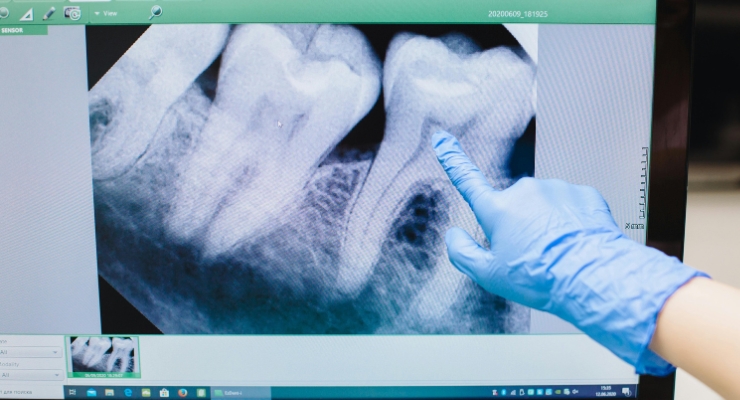

Prvi korak u liječenju je utvrđivanje točnog stanja i dijegnosticiranje upale. U ovom postupku značajan uvid u stanje daje nam snimka zuba.